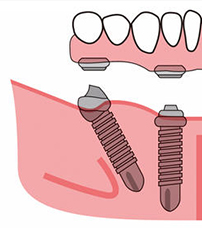

拔牙后医生冲洗了我的拔牙窝,后来就是种植体植入了,整个种牙的时间一个小时,我很安心的是种牙全程都有导航在检测医生的植入位置,根本不怕种植体会种歪,另外,我拔牙的数目比较多,术前医生跟我说,会植入些骨粉骨膜,这样牙槽骨和种植体能更好的愈合在一起,以后就会更稳固。

为了帮我马上戴牙,术后医生重新给我取了牙模,戴上临时树脂牙冠后重新调整了咬合关系,这样术后吃喝就没有问题了,来这种牙之前我也对“即刻用、当天用”抱有怀疑,亲身经历后方知确有其事。

2、术后2小时后(麻醉消散后)是可以吃流食的,虽然说是拔牙即刻用,但其实种植体和牙槽骨没有愈合好,太硬的食物肯定会松脱的,温度也要适宜,你们可以看下图,种植体植入后,还需要基台和临时冠,没有稳固结合的种植牙,吃不了硬物。